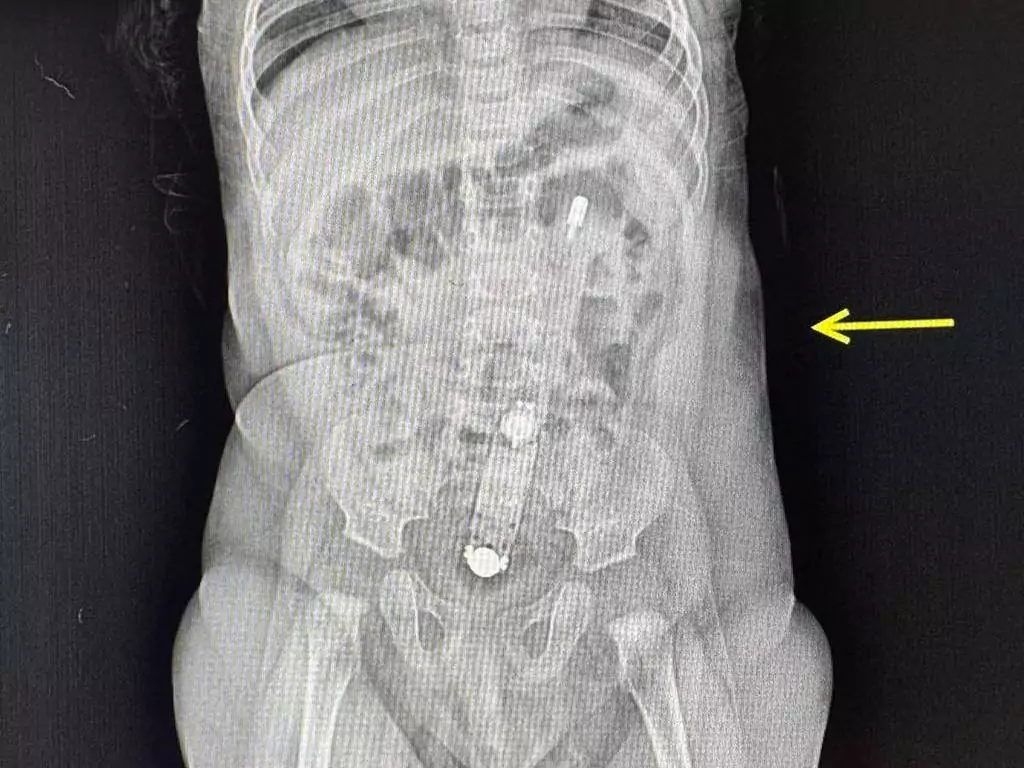

У Нововолинську лікарі провели операцію пацієнтці, яка раптово втрачала свідомість і пережила клінічний стан через тромб у легенях. Про це повідомили Нововолинській центральній міській лікарні. До КНП «Нововолинська ЦМЛ» у важкому стані доставили жінку з Львівщини. Після травми попереку та тривалого ...